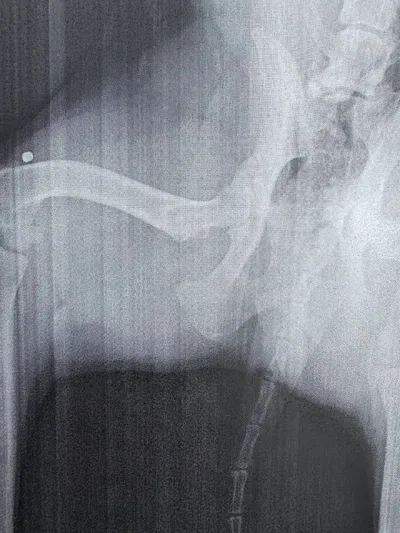

Короче говоря, Френка повели на рентген, потому что он начал прихрамывать. И обнаружили в его задней лапе… пулю. Вы вообще можете себе такое представить? 🤯 Теперь сидим и думаем, сколько же всего он

Время охренительных историй! На этот раз отличился Френк. Он, конечно, умеет удивлять… но сейчас дело серьёзное 😬 Вы знаете, куда нажимать, чтобы мы всё вам рассказали!